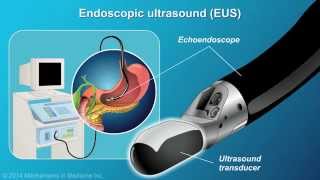

EUS-FNA and evaluation of a pancreatic cancer.

EUS-FNA and evaluation of a pancreatic cancer. Understanding EUS-FNA

Understanding EUS-FNA EUS-Guided Fine Needle Biopsy of a Pancreatic Mass

EUS FNA of a pancreatic tumor with wet suction technique - EndoClubNord 2018 Pancreatic Cancer -- Advanced EUS Imaging: Real-Time EUS Elastography

Pancreatic Cancer -- Advanced EUS Imaging: Real-Time EUS Elastography What is EUS/FNA? How does this help with pancreatic cancer treatment? (Kulwinder Dua, MD)

What is EUS/FNA? How does this help with pancreatic cancer treatment? (Kulwinder Dua, MD) When is EUS-FNA used?

When is EUS-FNA used? EUS-Guided Fine-Needle Aspiration for the Diagnosis & Staging of Pancreatic Masses